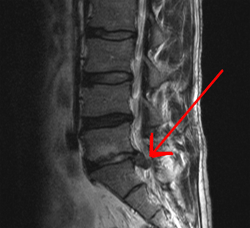

大概也是兩天過後去看報告,醫生把影像一格一格放出來,畫面像是身體切片那樣由上往下看,很清楚的可以看到有一截往左邊突出的影子,另一個是側身的畫面,本來是想讓大家看一下我的核磁共振圖片,但是...光碟機很不合作,讀不出來QwQ(好吧其實我的光碟機壞掉很久了),幸好wiki上有一張很像的圖片

箭頭指向的突出物,就是骨頭和骨頭之間的軟骨,正常來說它應該是亮灰色的,代表裡面有水分,是健康的。但如果是像圖中那樣,就是椎間盤突出,而我的狀況是它不只是突出,影像照出來也變成暗灰色(沒有水份,無法有彈性的在上下的骨頭之間做緩衝),暗灰色就是表示軟骨開始缺乏水分,有退化的現象。

而且我還不只是一個軟骨出問題,上方和上上方骨頭之間的軟骨也開始有一點突出來且變成深灰色的跡象,但目前最嚴重的就是下方已經突出太多壓迫到的那一截必須要做處理。